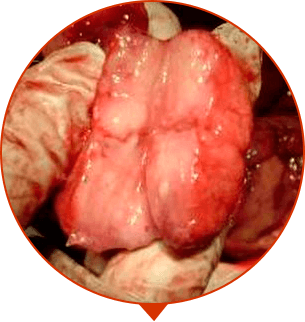

PROSTAT ADENOMASI

Prostat dokusunun büyümesi, tümör ve 'kütle' oluşumu